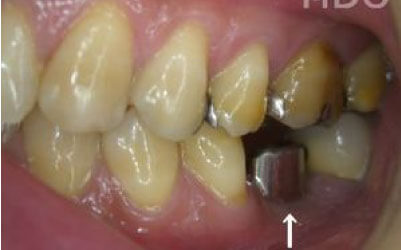

最も大きな違いは、前後の歯の寿命に影響が出ることです。

ブリッジの場合、抜けた歯の前後にある歯を、重度の虫歯と同じくらいまで削る必要があります。

また、抜けた歯の代わりに前後の歯が力を支えるため、その歯に常に1.5倍の負荷がかかります。

1)ブリッジ

2)歯を大きく削る+支えの歯に1.5倍の力がかかる

3)前後の歯の寿命が著しく減る

ブリッジの支えの歯は、データでは10年以内に68%が抜歯になります。